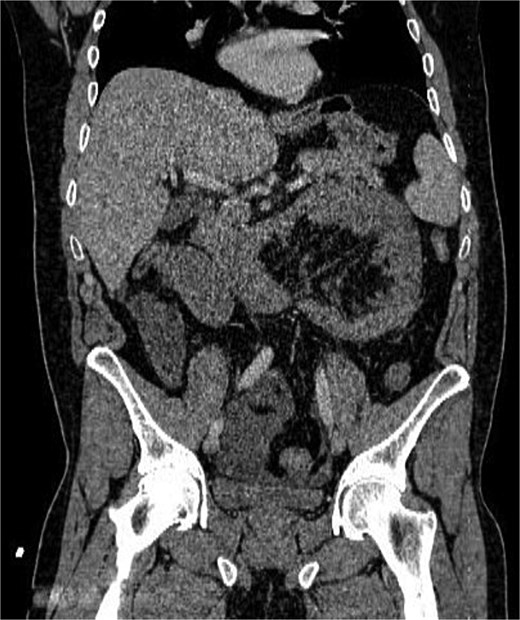

Abdominal radiography was non-contributory. Ultrasound demonstrated thickened small-bowel loops with inter-loop and minimal pelvic free fluid. Laboratory values showed WBC 20000/μl, Hb 15.4 g/dl, and platelets 417 × 109/l. Contrast-enhanced CT, despite limited field-hospital imaging capability, revealed a sac of clustered jejunal loops in the left upper quadrant beneath the superior mesenteric artery, consistent with a LPDH causing closed-loop obstruction (Figs 1 and 2).

Coronal CT image showing clustered jejunal loops in the left abdomen with mass effect and convergence of mesenteric vessels toward the hernia orifice.

This case illustrates the classical progression of LPDH from occult congenital anomaly to sudden closed-loop obstruction with necrosis. In keeping with the early radiologic descriptions by Suchato et al. and Osadchy et al., our patient’s CT demonstrated clustered loops beneath the SMA and convergence of mesenteric vessels, even though overt ischemia was not visualized [1, 2]. The discrepancy between imaging and operative findings is well documented, reinforcing the need for clinical judgment when strangulation is suspected.